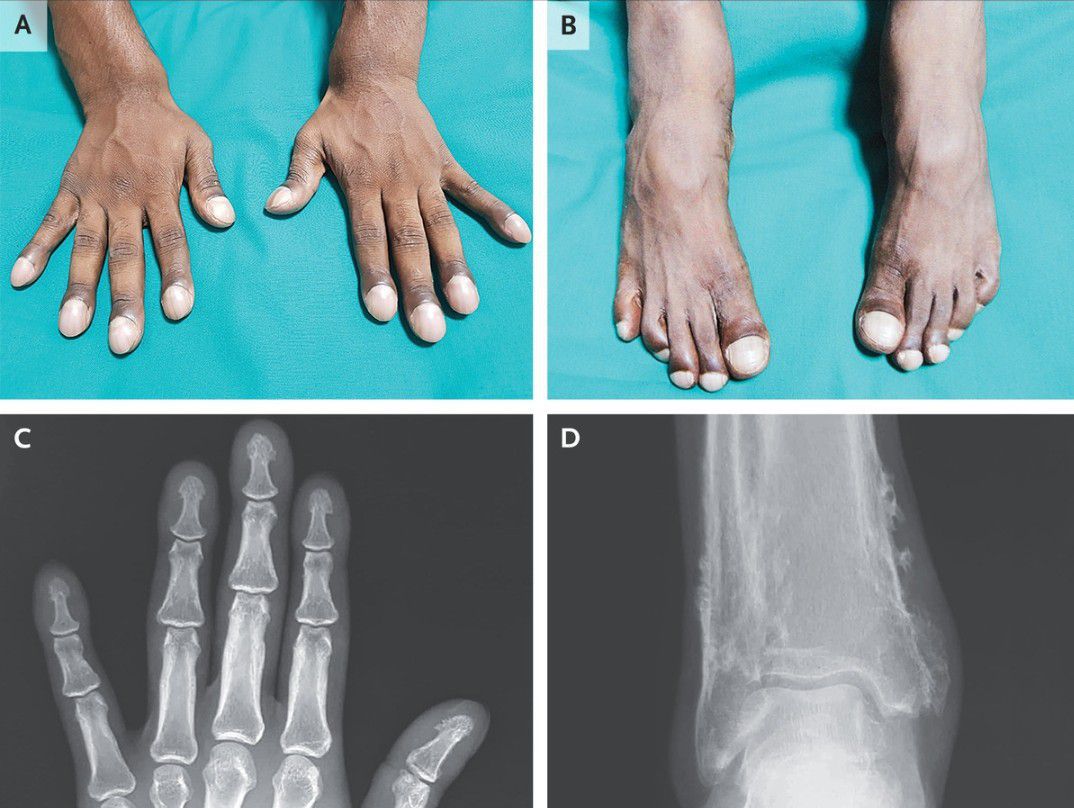

A 31-year-old man presented to the internal medicine clinic with 10 years of progressive enlargement of his fingertips and toes and intermittent aches in his distal forearms and lower legs. He had no clinically significant medical history or family history of similar symptoms. Finger and toe clubbing, with a supranormal angle of 210 degrees between the nail bed and the proximal nail fold, was observed on examination. Hyperpigmentation of the proximal nail folds; tenderness to palpation of the distal forearms and lower legs, fingertips, and toes; and widening of the distal forearms and lower legs (Panels A and B, respectively) were also observed. There was no skin thickening or hyperhidrosis. Radiographs of the fingers showed bony proliferation at the tips of the phalanges (Panel C), and radiographs of the ankles showed increased periosteal bone formation at the distal tibia and fibula (Panel D). Serum laboratory tests (including thyroid-function studies), an echocardiogram, and whole-body positron-emission tomography–computed tomography were normal. The patient received a diagnosis of primary hypertrophic osteoarthropathy, a hereditary syndrome characterized by clubbing, periosteal bone proliferation, and (not seen in this case) facial skin thickening and hyperhidrosis, in the absence of systemic conditions. The patient was initially treated with nonsteroidal antiinflammatory drugs for 3 months. Given persistent symptoms, zoledronic acid was administered, and his pain had abated at follow-up 2 months later.